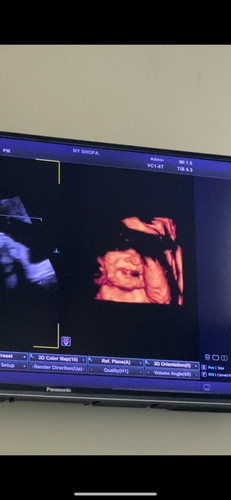

Alhamdulillah bun udah lahiran. Pembukaan dri jm 11 mlm smpai 4 sore masih 2 jd induksi infus dan telah lahir putri pertama kami di tgl 13-032023 BB 3.1kg usia kandungan 38mg 3hari🤲🏻😇perjuangan yg masyaallah krna udah gk kuat ngeden ibu nya jd divakum ngeden trakhir sampe pendarahan+bonus jahitan☺️ #firstmom